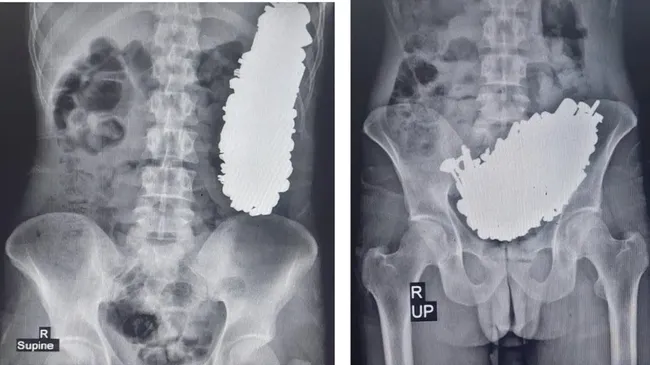

Foto: Pria menelan 452 benda logam (Journal of Medical Case Report)

Para dokter melaporkan sebuah kasus yang mencengangkan, yakni ada ratusan benda logam dalam perut seorang pria di Iran. Total ada 452 benda logam yang terdiri dari sekrup, mur, kunci, dan lainnya, dengan berat 2,9 kg.

Dilansir detikHealth, hasil Sinar-X menunjukkan massa logam menghalangi jalan keluar lambung pria berusia 36 tahun itu. Hal ini yang menyebabkannya sakit perut kronis dan sering muntah sehingga dia tidak bisa makan atau minum. Kasus ini diterbitkan dalam Journal of Medical Case Reports.